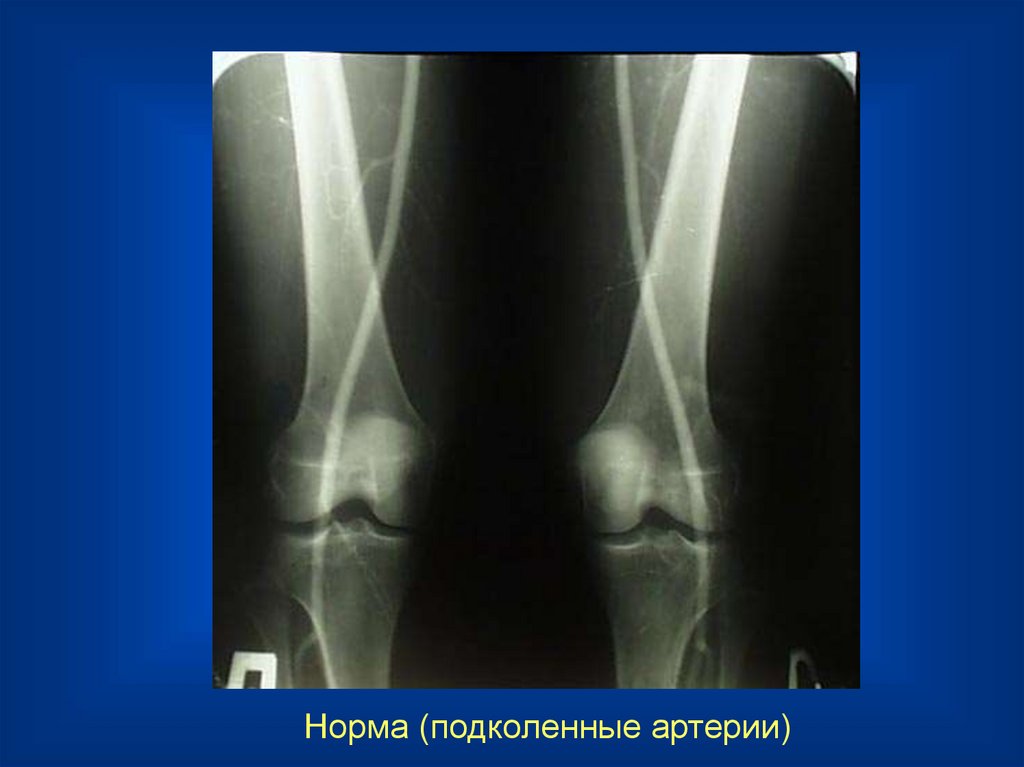

Норма (подколенные артерии)